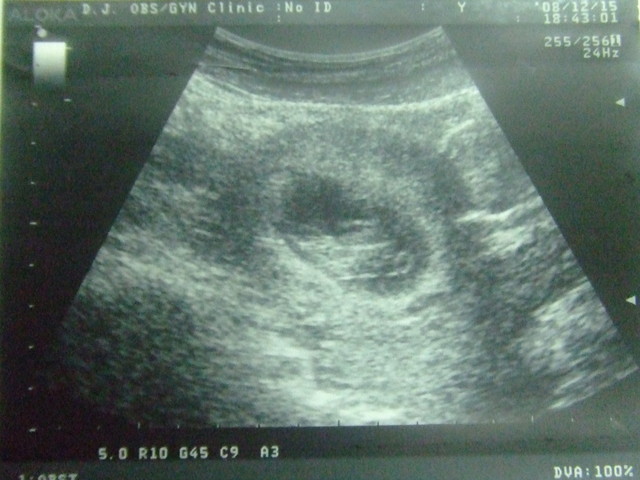

baby~今天又看到妳了~

想不到妳又長大好多!!

現在已經約26mm了耶~

一個禮拜長12mm~不錯!!

還有林醫師幫妳掃了一下頸後透明帶約0.1cm~正常的!

卵黃囊也快消失囉~再來就是靠臍帶連接胎盤攝取營養了~